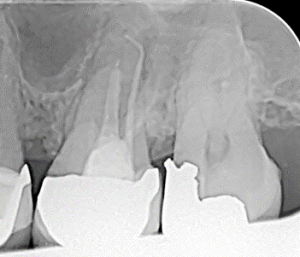

Clinical Cases